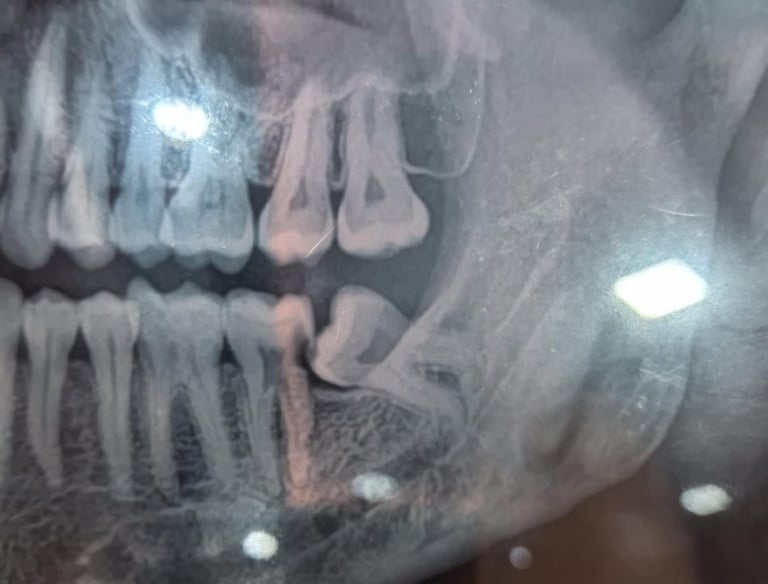

Impacted teeth may be monitored if symptom-free. Surgery is common for wisdom teeth, while orthodontic aids can help guide tooth eruption.

Impacted Tooth Surgery